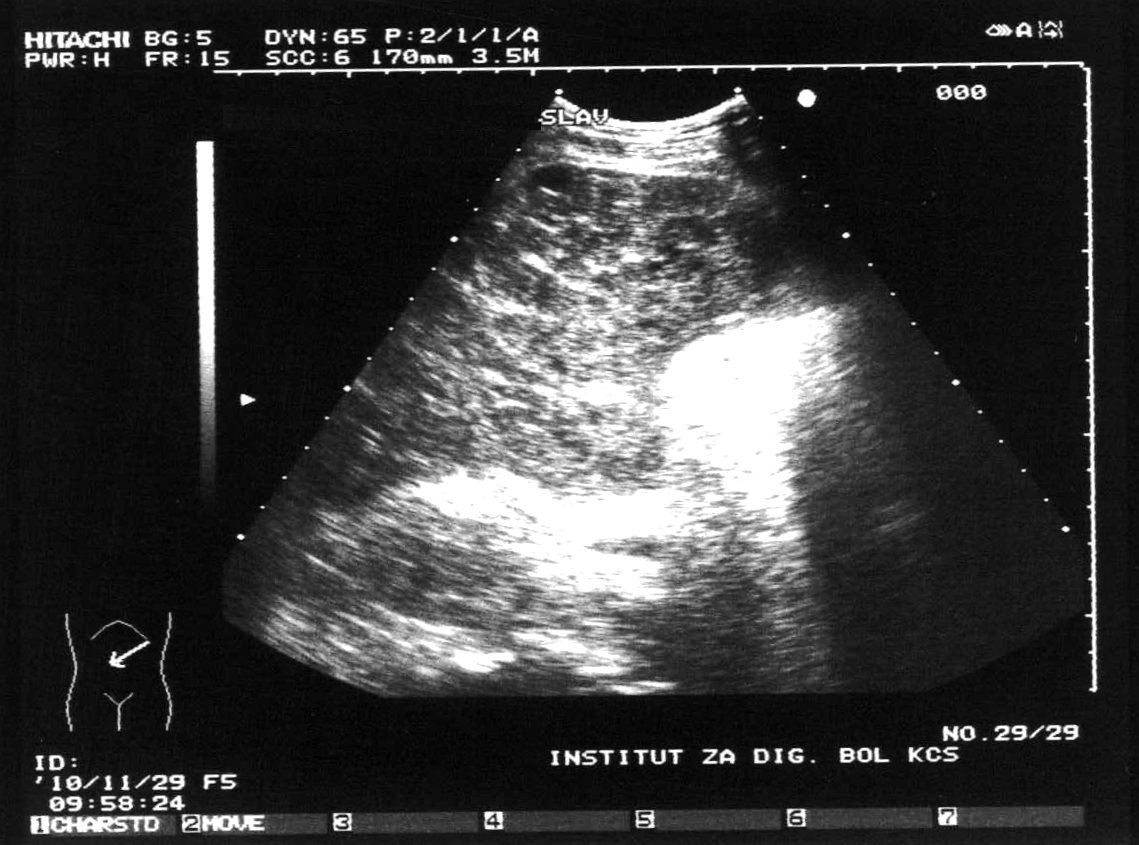

Boricic, Ivan